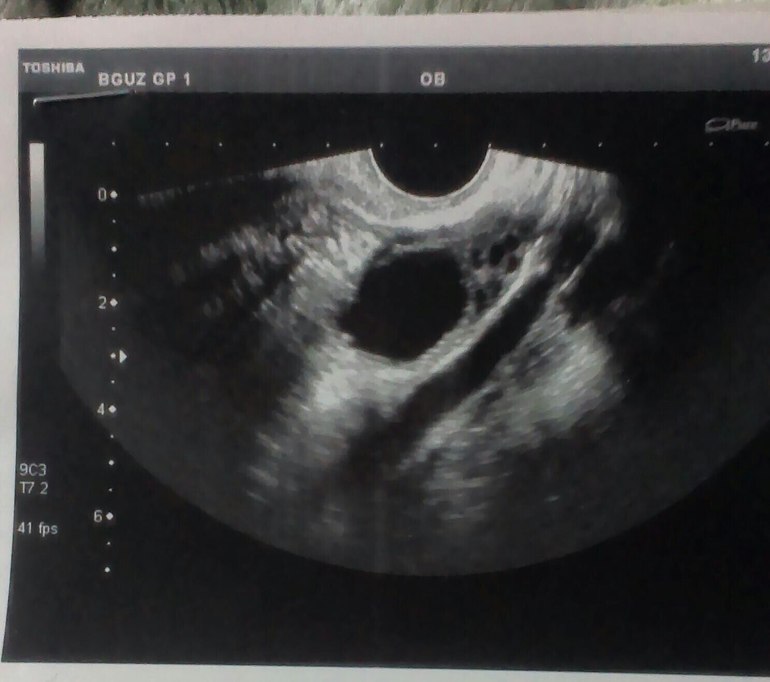

ФолликулометрияСделала вчера узи 23 дц.Была лапароскопия 22.10 по поводу Спяк,в этот же день начались выделения кровавые я их сочла за месячные.Вот вчера сходила на узи и что имею я в замешательстве.Подскажите кто знает.

Анэхогенное образование это киста (скорее всего, потому что когда желтое тело так и пишут), а в правом похоже намечается овуляция))) будем надеяться что он еще раза в 2 -3 подрастет и лопнет)))

Когда ЖТ так и пишут.а как вам написали так обозначают кисту